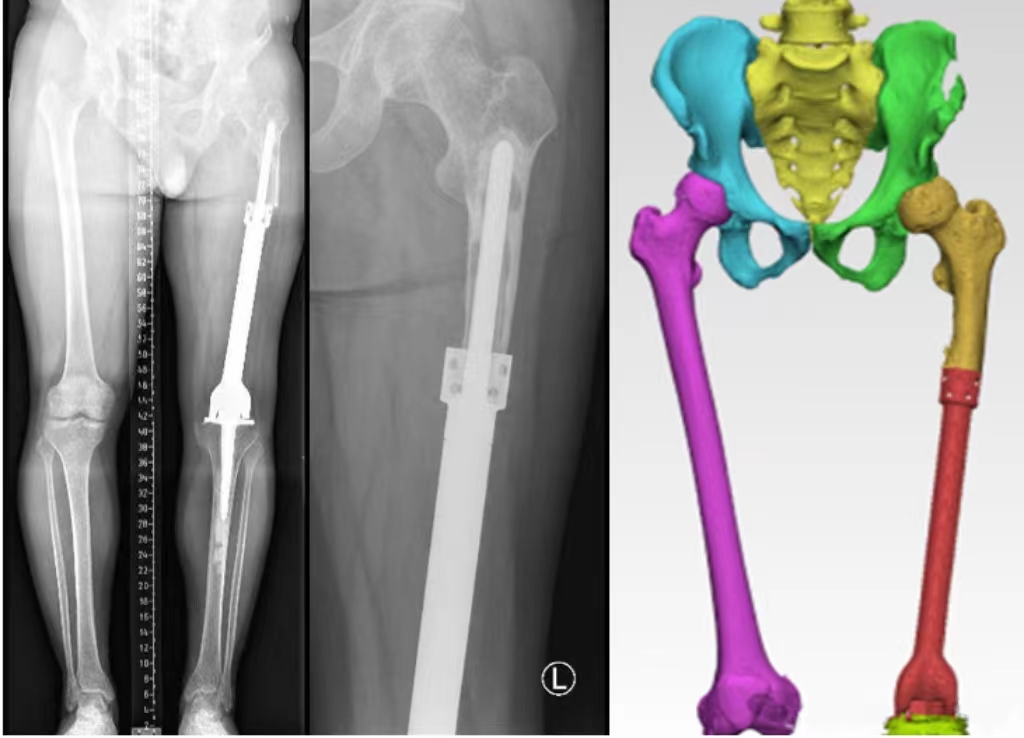

手术前影像资料

常黎明副院长详细介绍了3D假体的设计及手术方案。该设计是在原有假体的基础上,以最小的创伤,通过术前CT采集数据后,重建,建模后,精准地设计出与原假体及残留骨质完美结合的假体部件,再通过设计支持钢板,增加了该假体部件的稳定性,进一步防止假体松动,保证假体的长远使用效果和安全性,做到了肿瘤假体翻修的“微创、精准、个性化、保证牢固性”等特点。

3D 打印假体设计